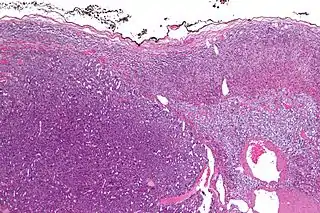

![]() Micrografía de un carcinoma adrenocortical (a la izquierda de la imagen, azul oscuro) y de la corteza adrenal de la que surgió (arriba a la derecha de la imagen, rosa / azul claro). La médula suprarrenal benigna está presente (mitad derecha de la imagen, gris/azul). Tinción H&E. | ||